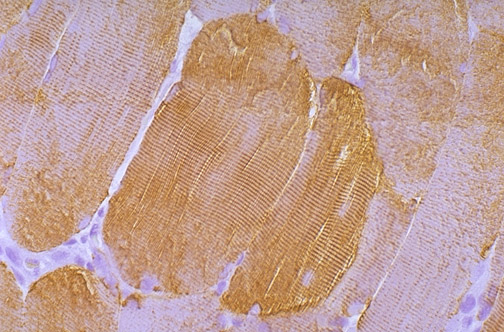

| This is normal skeletal muscle with immunohistochemical staining using antibody to desmin. Desmin, along with vimentin, is an "intermediate" filament between the size of thin actin and thick myosin. Both desmin and vimentin secure the periphery of Z disks to adjacent myofibrils. Another protein, dystrophin, binds actin and aids in attaching bundles of myofibrils to the sarcolemma. |